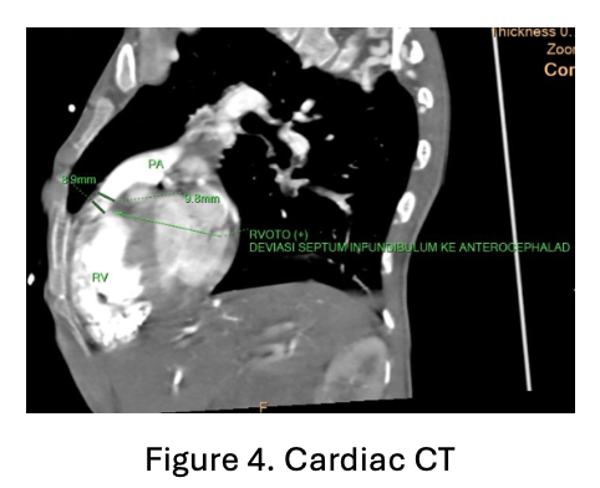

An 8F sheath was inserted into the femoral vein and an arterial line was placed in the femoral artery. Intraoperative transesophageal echocardiography (TOE) showed a very tight right ventricular outflow tract (RVOT) measuring 23.7 mm in length, with a left ventricular ejection fraction (LVEF) of 51.7% by Simpson¡¯s method. RVOT angiography performed using a 3.5/5F Guiding JR catheter confirmed narrowing at the RVOT segment.